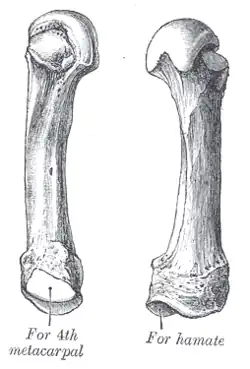

The fifth metacarpal. (Left.) | |

The fifth metacarpal bone (metacarpal bone of the little finger or pinky finger) is the most medial and second-shortest of the metacarpal bones.

It presents on its base one facet on its superior surface, which is concavo-convex and articulates with the hamate, and one on its radial side, which articulates with the fourth metacarpal.

On its ulnar side is a prominent tubercle for the insertion of the tendon of the extensor carpi ulnaris muscle.

The dorsal surface of the body is divided by an oblique ridge, which extends from near the ulnar side of the base to the radial side of the head. The lateral part of this surface serves for the attachment of the fourth Interosseus dorsalis; the medial part is smooth, triangular, and covered by the extensor tendons of the little finger.

The palmar surface is similarly divided: Its lateral side (facing the fourth metacarpal) provides the origin for the third palmar interosseus, its medial side contains the insertion of opponens digiti quinti.